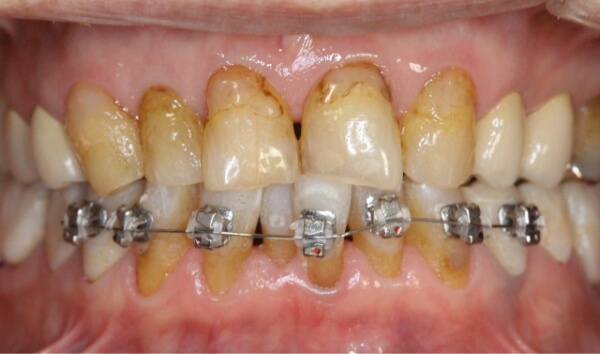

歯は削らずにブラケットを使用して、上下の前歯6本の隙間を閉じる治療を始めることになりました。

矯正装置(ワイヤーと審美ブラケット)をつけた当初は、少し痛みや違和感があったそうですが、歯が動き始めると痛みや違和感は次第になくなっていきました。

術中